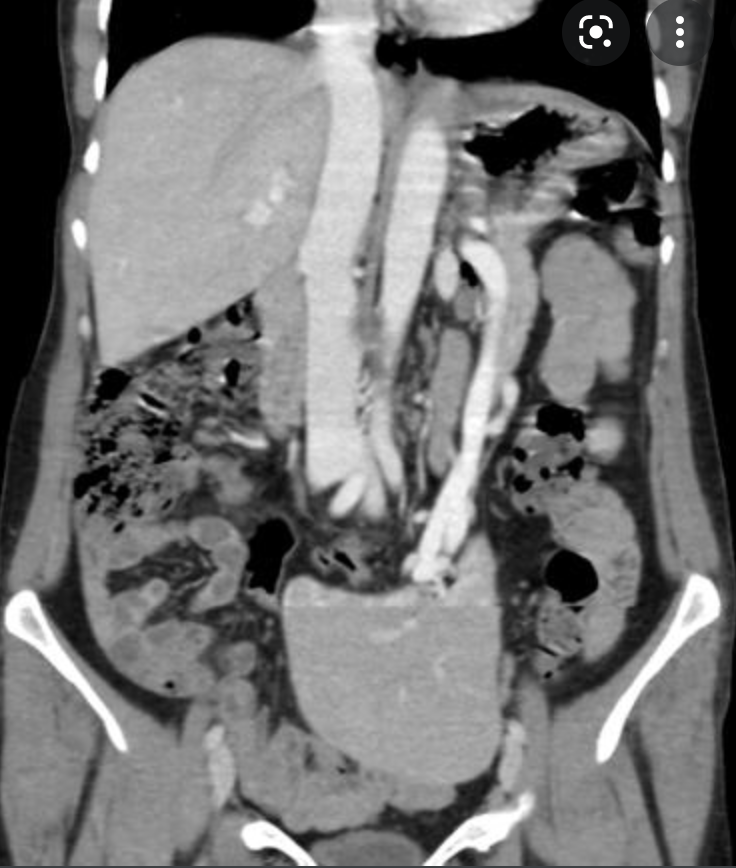

What grade Splenic injury is this?

Extensive splenic lacerations extending to the hilum with areas of devascularisation. No evidence of active bleeding or pseudo-aneurysm. There is extensive haemoperitoneum throughout the abdominopelvic cavity. Cholecystectomy clips are noted along with extrahepatic and first order intrahepatic duct dilatation. Liver is uninjured. Adrenal glands, kidneys and pancreas are uninjured. Bowel is unremarkable. Lung bases are clear. No bony injury identified.

Conclusion:

AAST grade IV splenic injury with extensive haemoperitoneum.

Case Discussion

Further history obtained (after the CT) revealed a fall from 1.5 metres. Patient proceeded to successful splenic embolisation.